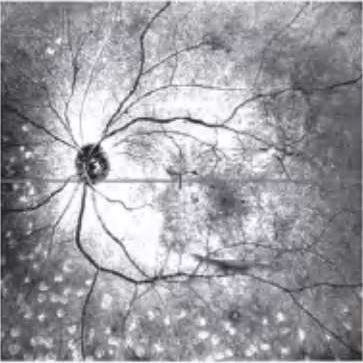

图2-2-1 抗VEGF及PRP治疗后玻璃体后脱离范围显著扩大的PDR案例

A.PDR合并玻璃体视网膜牵拉引发的相关DME,既往已行PRP,行4次抗VEGF药物治疗后,黄斑区玻璃体后界膜与视网膜分离(白色箭头所示),玻璃体视网膜牵拉解除,黄斑水肿较前明显好转。B.PDR合并玻璃体视网膜牵拉性相关DME,在行3次视网膜激光光凝治疗后,黄斑区玻璃体后界膜与视网膜分离(白色箭头所示),玻璃体视网膜牵拉缓解,黄斑水肿较前好转。